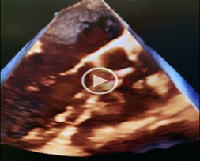

An aneurysm of Sinus of Valsalva (most commonly right sinus) is a rare finding, which may be congenital or acquired. A ruptured Sinus of Valsalva aneurysm (RSOVA) may lead to serious complications including myocardial ischemia, obstruction of right ventricular outflow tract and cardiac tamponade and warrants urgent repair – either surgical or percutaneous. We present a case which was pre-diagnosed with VSD and referred to our centre where clinical

evaluation revealed continuous murmur and on transthoracic echocardiography a large left to right shunt with continuous flow (predominant diastolic flow) was observed. It was only diagnosed as a RSOVA when Transesophageal echocardiography (TEE) was performed when patient was taken to Cath lab for urgent percutaneous device closure of septal defect.  Although rare, a missed diagnosis of RSOVA can be catastrophic as it has serious consequences and warrants urgent repair – either surgical or percutaneous. The role of TEE cannot be undermined in its diagnosis.